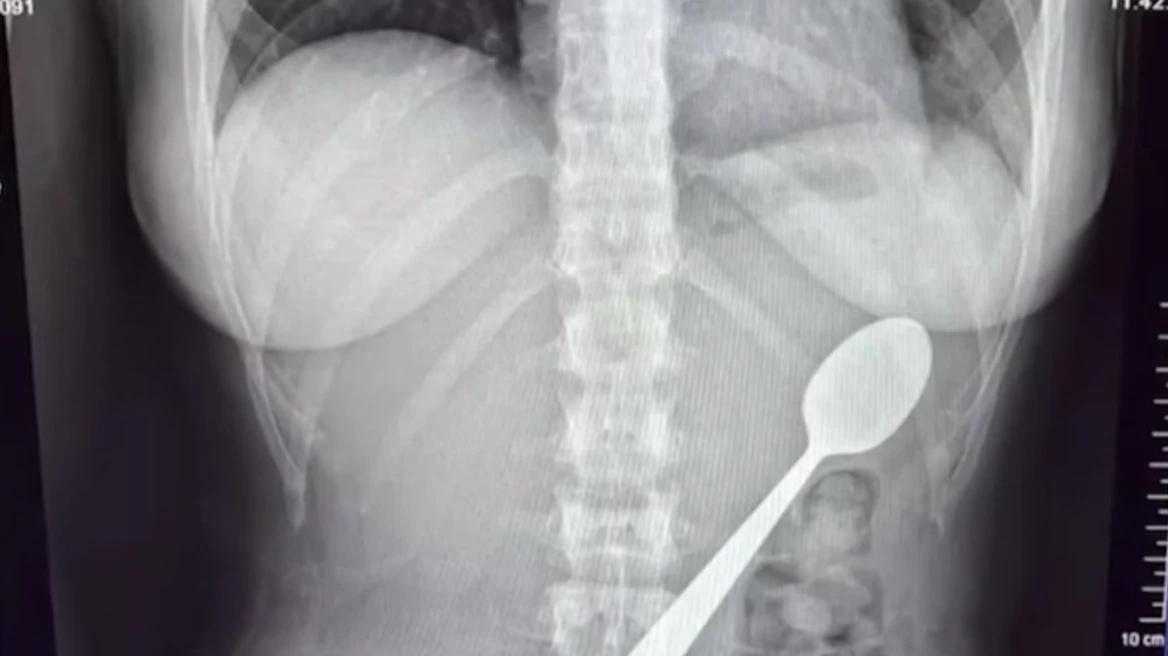

Κρατούσε το κουτάλι στο στόμα της ενώ απαντούσε σε μήνυμα στο κινητό της. Σύμφωνα με την ίδια, ο σκύλος της, ένα ουγγρικό Βίσλα με το όνομα Μάρλεϊ, πλησίασε απότομα και πήδηξε πάνω της, με αποτέλεσμα το κεφάλι της να γείρει προς τα πίσω και το κουτάλι να σφηνωθεί στον λαιμό της. «Έπρεπε να διαλέξω αν θα το καταπιώ ή θα πνιγώ», είπε περιγράφοντας τις στιγμές πανικού. Παρά τις προσπάθειες να το αφαιρέσει αμέσως, οι συνθήκες εξελίχθηκαν μέσα σε λίγα δευτερόλεπτα και η γυναίκα κατέφυγε στο να το καταπιεί για να αποφύγει ασφυξία.

Αρχικά η 28χρονη δεν ένιωσε έντονη δυσφορία και δεν αποκάλυψε το συμβάν όταν επέστρεψε ο σύντροφός της. Μετά το δείπνο ωστόσο παρουσίασε επιδείνωση συμπτωμάτων και ζήτησε ιατρική βοήθεια. Οι διαγνωστικές εξετάσεις έδειξαν ότι το κουτάλι ήταν πολύ μεγάλο για να αποβληθεί φυσιολογικά και οι γιατροί αποφάσισαν την αφαίρεση με γαστροσκόπηση. Οι απεικονιστικές και ενδοσκοπικές εξετάσεις επιβεβαίωσαν τη θέση του αντικειμένου και την αδυναμία αυτόματης διέλευσής του. Το διάστημα μέχρι την επέμβαση, διάρκειας δύο ημερών, η ασθενής ανέφερε αίσθημα ότι το αντικείμενο κινούταν μέσα στο σώμα, φούσκωμα, ναυτία και έντονη δυσφορία. Η ενδοσκοπική επέμβαση πραγματοποιήθηκε υπό γενική αναισθησία και περιλάμβανε περιστροφή του μεταλλικού αντικειμένου μέσα στο στομάχι ώστε να εξασφαλιστεί η ασφαλής πρόσβαση και η έξοδος του. Κατά τη διαδικασία σημειώθηκε μικρή γαστρική αιμορραγία που αποδόθηκε στην κίνηση του κουταλιού, αλλά η αφαίρεση ολοκληρώθηκε με επιτυχία και χωρίς περαιτέρω άμεσες επιπλοκές. Η ασθενής παρέμεινε υπό ιατρική παρακολούθηση μετά την επέμβαση.